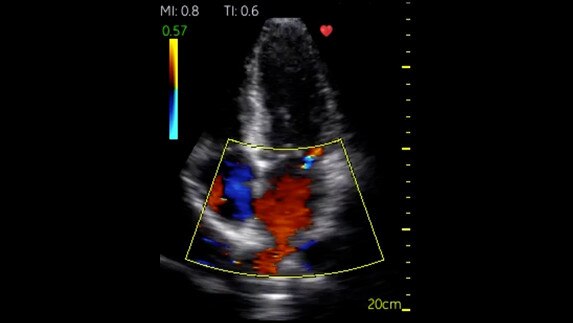

Fazlı Kardiyak